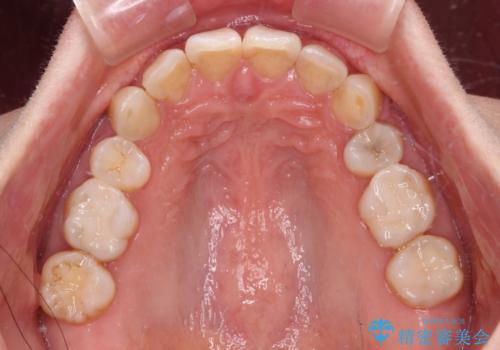

- 以前行った抜歯矯正が後戻りし、開いてしまったスペースが気になるとのことで来院された患者様です。

インビザラインを用いて開いてしまったスペースと前歯のデコボコを改善することとしました。

矯正治療後には気になっていた銀歯をセラミッククラウンやセラミックインレーにて治療することとしました。

上顎前歯を左右対称となるように歯列を整えたいとのことでしたが、すり減って形態が大きく異なっていたため、できる範囲での仕上がりとなりました。